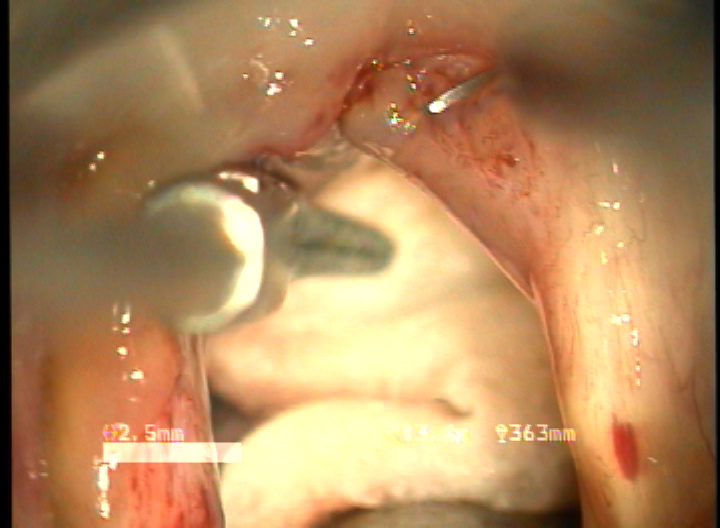

목적 : 전성문횡격막(anterior glottic web)은 선천성이나 수술과 같은 이차적인 원인에 의해서 발생되는 난치성 후두질환이다. 또한 기존의 치료방법으로는 음성개선의 효과가 매우 낮은 결과를 얻고 있다. 이에 음성의 보존과 함께 일차적 시술로서 치료가 가능한 double rotation microflap 을 이용한 새로운 술식을 보고하며, 이술식의 치료결과와 음성학적 개선을 알아보고자 하였다.

방법 : 2006년 1월 부터 2007년 12월 까지 예송이비인후과에서 전성문횡격막으로 진단되어 double rotational microflap laryngoplasty를 시행받고 1년간 장기추적이 가능하였던 6명의 환자를 대상으로 후향적 분석을 시행하였다. 원인적인 요인과 동반질환으로는 후두유두종 술후 합병증 4례, 후두외상 1례, 폴립양성대 1례 였다. 남녀 각각 3례였으며, 평균연령은 39세 였다. 추적기간은 21.5 개월이었다. 술 후 2개월과 6개월에 음성개선에 대한 주관적인 음성평가를 시행하였으며, 음성분석검사와 후두스트로보스코피 검사를 통하여 객관적인 음성평가와 성대점막파동의 변화를 관찰하였다. 통계적 유의성은 Wilcoxon Signed Ranks Test로 검정하였다.

결과 : 음성개선에 대한 주관적인 평가로서 수술전 Voice Handicap Index는 평균 19.7 에서 술후 11.5로 감소하였다. 공기역학적인검사상 성문하압은 5.5에서 4.5로 감소되었으며, 최대발성시간 13.7에서 16.1로 증가되었다. 음성분석검사상 sPPQ, sAPQ, NHR, SPI, DSH가 모두 통계학적으로 유의하게 감소하였다. 후두스토로보스코피검사상 모든 례에서 재발의 징후없이 성대점막파동의 의미있는 호전이 나타났다. 합병증으로 1례에서 염증성 육아종형성이 관찰되었으나 미세피판의 괴사나 탈락은 관찰되지 않았다.

결론 : 전성문횡격막의 새로운 수술방법으로서 double rotational microflap laryngoplasty는 일차수술로 만족스러운 음성학적 치료결과를 얻을 수 있는 매우 유용한 술식이라 사료된다.